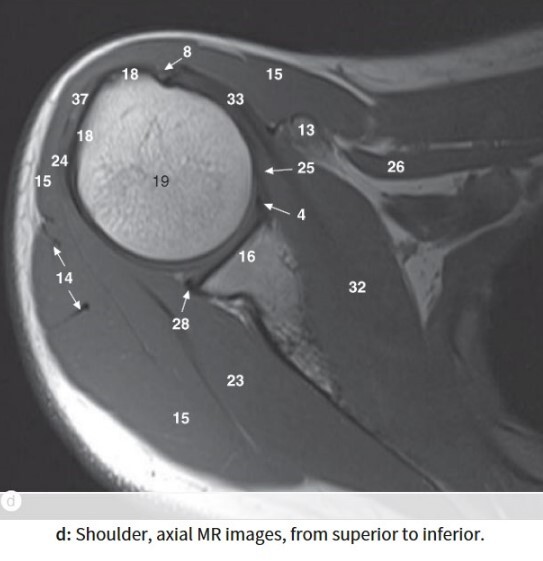

Label 16,18,19,23

16=Glenoid process of Rt. scapula

18=Greater tubercle of Rt. humerus

19=Head of rt. humerus

23=Rt. infraspinatus muscle

Label 13,15,16,18,19,23,32

13=Rt. coracoid process

15=Rt. deltoid muscle

23= Rt. infraspinatus muscle

32=Rt. subscapularis muscle